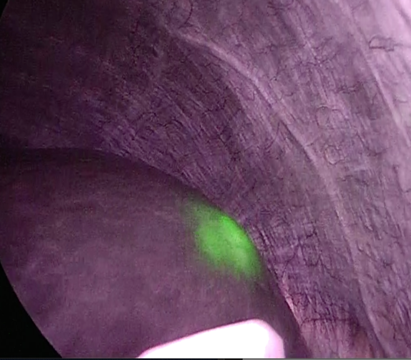

腹腔鏡下肝切除でのICG蛍光イメージング(IR)システム使用について

手術の1週間前に肝機能検査で投与したICG(インドシアニングリーン)が肝臓の腫瘍に集積し、近赤外線カメラで観察すると腫瘍が蛍光発色して同定されます。腫瘍の位置を正確に把握したり術前診断で描出されていなかった腫瘍を手術中に発見することができます。当院は2018年から導入し使用しています。

術中初見 : 手術前の検査では診断できなかった小さな癌が手術中に判明した肝細胞癌の例。